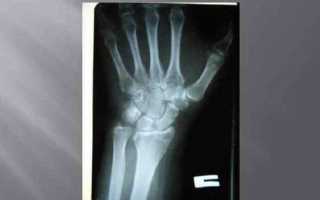

На первоначальном этапе врач собирает анамнез заболевания, в процессе беседы с пациентом уточняет обстоятельства падения и время. Далее производит осмотр, после которого пострадавший направляется на рентгенографию лучезапястного сустава в двух проекциях (прямой и боковой).

Для того чтобы оценить правильность срастания костных отломков, через неделю после травмы и перед снятием гипса назначают контрольную рентгенографию.